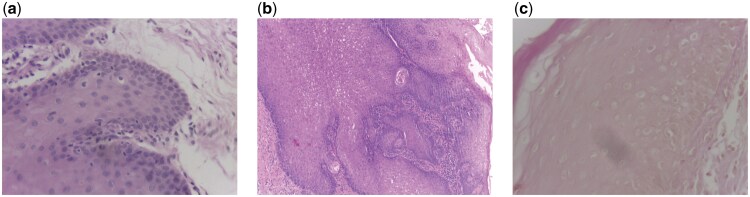

This study introduces an approach to classifying histopathological images for detecting dysplasia in oral cancer through the fusion of support vector machine (SVM) classifiers trained on deep learning features extracted from InceptionResNet-v2 and vision transformer (ViT) models. The classification of dysplasia, a critical indicator of oral cancer progression, is often complicated by class imbalance, with a higher prevalence of dysplastic lesions compared to non-dysplastic cases. This research addresses this challenge by leveraging the complementary strengths of the two models. The InceptionResNet-v2 model, paired with an SVM classifier, excels in identifying the presence of dysplasia, capturing fine-grained morphological features indicative of the condition. In contrast, the ViT-based SVM demonstrates superior performance in detecting the absence of dysplasia, effectively capturing global contextual information from the images. A fusion strategy was employed to combine these classifiers through class selection: the majority class (presence of dysplasia) was predicted using the InceptionResNet-v2-SVM, while the minority class (absence of dysplasia) was predicted using the ViT-SVM. The fusion approach significantly outperformed individual models and other state-of-the-art methods, achieving superior balanced accuracy, sensitivity, precision, and area under the curve. This demonstrates its ability to handle class imbalance effectively while maintaining high diagnostic accuracy. The results highlight the potential of integrating deep learning feature extraction with SVM classifiers to improve classification performance in complex medical imaging tasks. This study underscores the value of combining complementary classification strategies to address the challenges of class imbalance and improve diagnostic workflows.